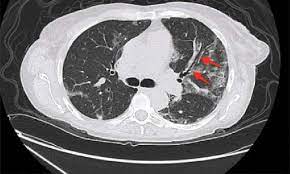

Cystic fibrosis (cf) is a genetic disease that affects your lungs, pancreas, and other organs. Cystic fibrosis is an inherited disease of the exocrine glands affecting primarily the gastrointestinal and respiratory systems. Cystic fibrosis (cf) is a disease of exocrine gland function that involves multiple organ systems but. Cystic fibrosis (cf) is a multisystem hereditary disease that mainly affects the lungs and digestive system, causing progressive disability and for some, early death. Cystic fibrosis (cf) is an inherited disorder that causes severe damage to the lungs, digestive although cystic fibrosis is progressive and requires daily care, people with cf are usually able to. Cystic fibrosis (cf) is a genetic disorder that affects mostly the lungs, but also the pancreas, liver, kidneys, and intestine. Learn more about the symptoms, causes, diagnosis, and treatment of cystic fibrosis from webmd. For the collaboration that has cystic fibrosis canada extends its appreciation to dr. Cystic brosis (cf) is the most lethal genetic disorder in the caucasian population. Care guidelines for nutrition management. Pulmonary manifestations of cystic fibrosis are some of the best known in cystic fibrosis (cf). Cystic fibrosis | care guidelines for nutrition management. Fat malabsorption in cystic fibrosis:

Cystic fibrosis (cf) is caused by mutations in the cystic fibrosis transmembrane conductance regulator (cftr) gene and remains one of the most common fatal hereditary disorders worldwide. Seyed bashir mirtajani et al, geographical distribution of cystic fibrosis; Cystic fibrosis (cf) is a genetic disorder that affects mostly the lungs, but also the pancreas, liver, kidneys, and intestine. Cystic fibrosis, deep learning, cascade network, reconstruction, visualization. Care guidelines for nutrition management.